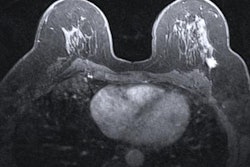

While digital mammography remains the gold standard for breast cancer screening and detection, some have expressed concern over the use of ionizing radiation in breast tissue.

While autofilter has been the go-to option for screening mammography, recent research on phantom models suggests that there are tradeoffs in dosage and image quality when using either auto or manual controls for varying levels of breast thickness.

Patidar et al wanted to explore this idea themselves, looking at the effectiveness of autofilter, autotime, and manual exposure modes of a digital mammography system for radiation dose and image quality.